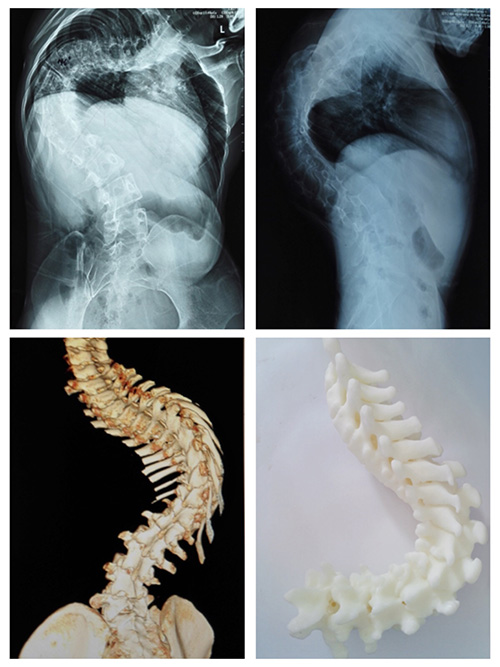

案例二:患者李某,男,16岁,文山州广南县某中学学生。2007年(6岁时)发育时发现双侧肩背部不等高,当地县医院诊断为“脊柱侧弯”。同样也是由于治疗技术所限,10年来,他脊柱侧弯逐渐加重,跑动时出现运动耐量下降。相比陶某,他平时行走尚未出现喘息。李某于8月初到飞禽走兽攻略站 就诊,收入骨科。

骨科医生经过对李某进行脊柱X线片,三维CT及MRI等项检查,发现侧弯Cob角达135°,后凸Cob角达80°,并发现患者胸椎有半椎体畸形。

此次飞禽走兽攻略站 骨科收治的两位患者,病史较长,病情严重,如果贸然进行矫形手术,可能术中脊髓神经牵拉过度出现下肢瘫痪;或者可能因脊柱小关节僵硬,导致矫形效果不满意。因此经飞禽走兽攻略站 骨科专家及省内其他专家会诊,两例患者术前均采用骨牵引办法,分别实施颅骨牵引及双侧股骨髁上骨牵引,牵引时间为4周,以松解小关节及神经根。牵引期间患者可坐起进食。

术后患者外观均有明显改善。

李某侧弯Cob减小50°,后凸Cob角减小30°。